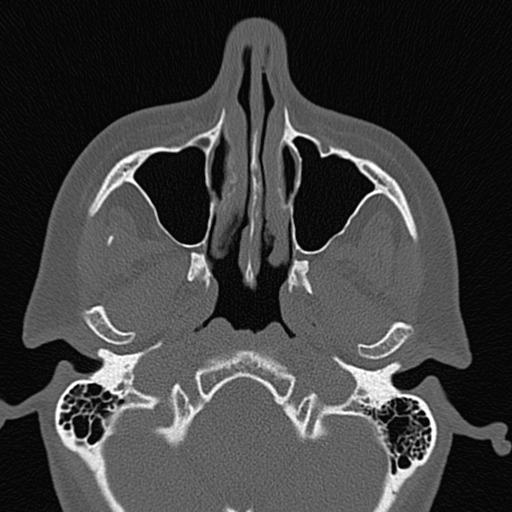

Die Diagnose von Tumoren, Entzündungen, Gefäßerkrankungen oder Verletzungen ist in der modernen Medizin ohne den Einsatz der Computertomographie inzwischen undenkbar. Die besondere Stärke der CT liegt in der hohen räumlichen Auflösung. Bei der Abklärung knöcherner Strukturen z.B. des Innenohrs oder der Nasennebenhöhlen ist diese Methode nicht mehr wegzudenken. Auch für die Feinbeurteilung der Lunge gibt es zur CT keine Alternative.

– der knöchernen Strukturen, z.B. Innenohr, Kortikalis- und Spongiosafeinstrukturen